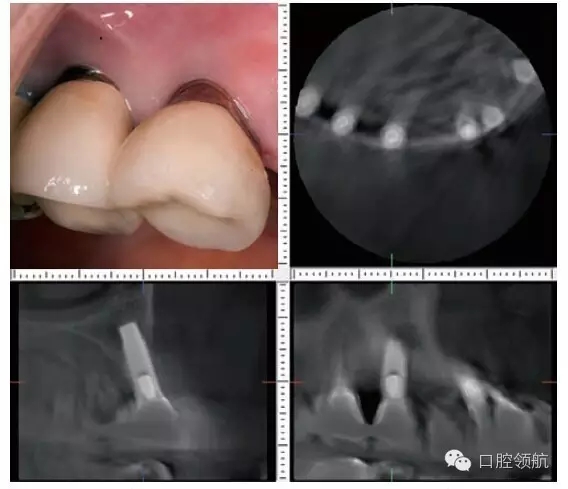

患者,66歲,女性。(左上第3顆牙)缺失的病例(圖1)(左上第4、5顆牙)部位已經(jīng)進(jìn)行了種植體修復(fù),從CBCT的影像診斷,(左上第4顆牙) 種植體頰側(cè)的骨吸收明顯,而且伴有周圍的軟組織的萎縮和種植體頸部的金屬暴露(圖2)。為了在(左上第三顆牙) 種植術(shù)后不再發(fā)生同樣的問(wèn)題,有必要進(jìn)行怎樣的處理呢?

圖2 (左上第4、5顆牙) 部位口腔內(nèi)頰側(cè)面觀(右上)和(左上第4顆牙)部位的CBCT各斷層影像,植入的位置偏頰側(cè)植入方向偏頰側(cè)傾斜,因此成為種植體頰側(cè)骨板的吸收原因,(左上第4、5顆牙) 種植體頸部的金屬暴露出來(lái)。